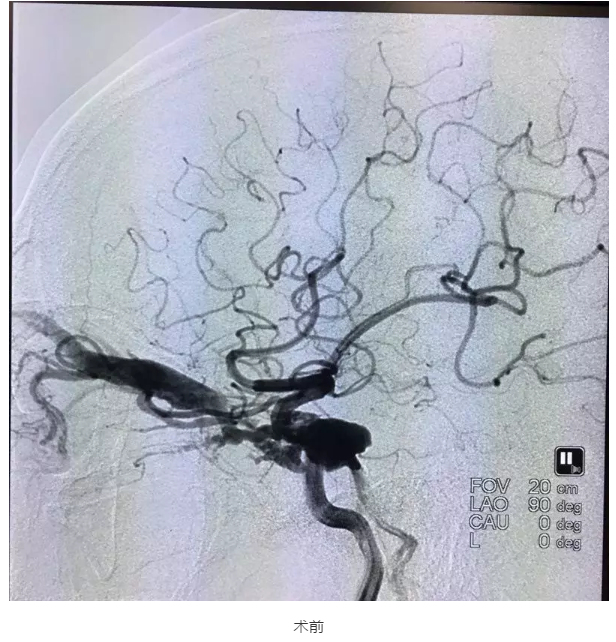

接诊的介入血管外三科向斌博士表示,入院时颜大爷右眼肿成球状、充血严重,眼睑外翻,裸露到眼眶外。经详细检查发现,患者脑内血管破裂,被诊断为颈动脉海绵窦瘘。通过精心准备,最终决定由刘觉仕主任、颜鹏主任、李志军副主任医师、向斌博士等组成的手术专家团队为患者实行颈动脉海绵窦瘘覆膜支架腔内修复术。

术中,经过精确测量及细心操作,成功的将支架置入患者颅内的颈动脉篓口处,成功的堵塞瘘口,再次造影显示瘘口完全被封闭。术后,患者眼部肿胀缓解,眼球回缩。目前,患者已顺利出院。